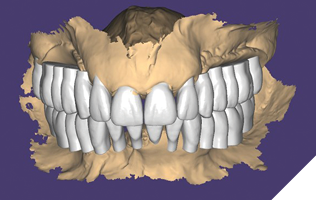

The data recorded during the clinical exam in conjunction with the FMS xrays and CT scan data were analyzed, and a diagnosis was made as to the viability of the patient’s existing teeth. A virtual diagnostic wax up was completed using prosthetic planning software (ExoCad) (Figs. 4A, 4B). The .STL file of the virtual wax up was integrated with the CT scan data in implant surgical planning software (3Shape Implant Studio) and a surgical plan was designed (Figs. 5A, 5B). The viability of this surgical plan was then evaluated in conjunction with the previously determined prognosis of the patient’s existing dentition and surrounding periodontium, and a treatment plan was formulated. The plan with the anticipated predictability of achieving the planned result was presented to the patient. The patient approved the treatment plan.

Fig. 4A

Fig. 4B